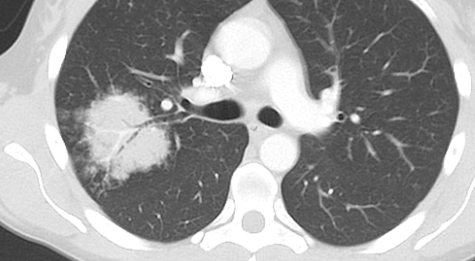

CT

round neumonie pneumonia